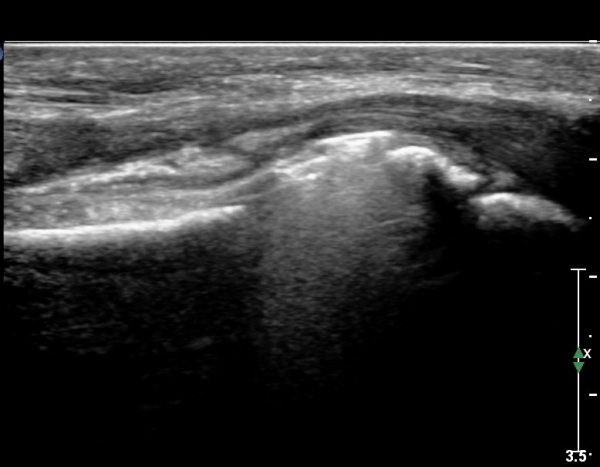

Å½ÃËÀÚ¸¦ ¾à°£ ³»ÃøÀ¸·Î À̵¿ÇÏ´Ï FPL ÈûÁÙÀÌ °íÁ¤¹°¿¡ ÀÇÇØ ¾Ð¹ÚµÇ°í ÀÖÀ½ÀÌ È®ÀÎµÇ°í ±ÙÀ§ºÎ¿Í ¸»´ÜºÎ´Â

Àú¿¡Ä¿ ºÎÁ¾ÀÌ °üÂûµÇ°í ±× »çÀÌ´Â °¡´Ã¾îÁ®¼­ ÈûÁÙÀÇ ¼Ò½Ç(ÆÄ¿­)À» ÃßÁ¤ ÇÒ ¼ö ÀÖÀ½(»çÁø 10. 11)